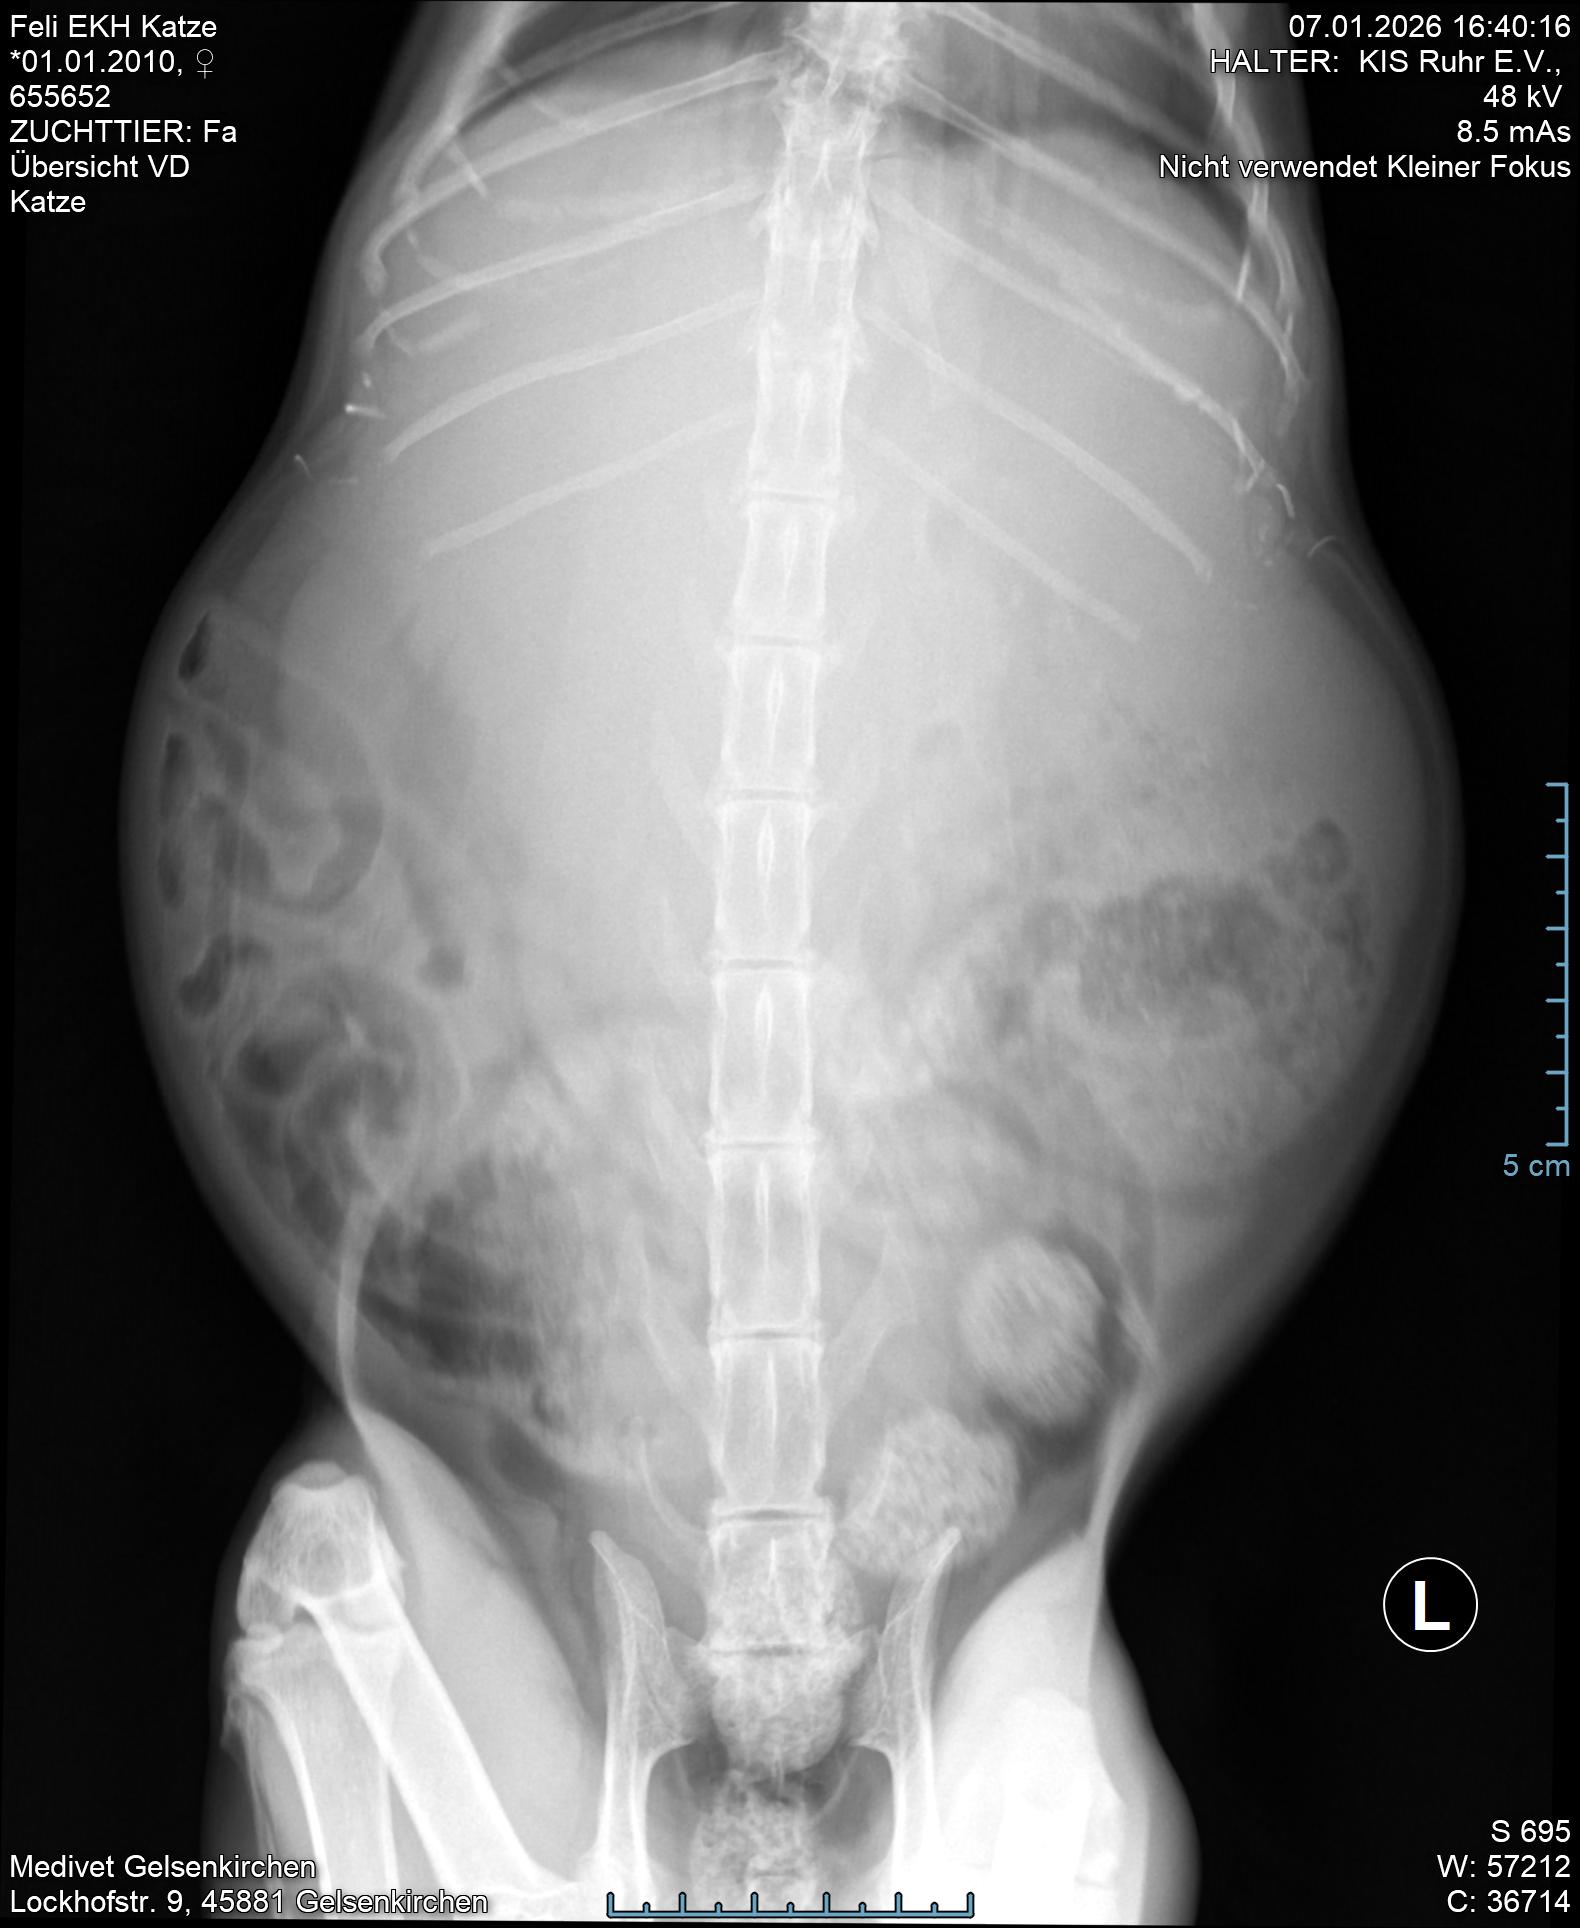

Die Ärztin fand den riesigen Lebertumor sofort. Ebenso hatte Feli erwartungsgemäß Spondylosen, ein Herzgeräusch und vermutlich kaputte Nieren.